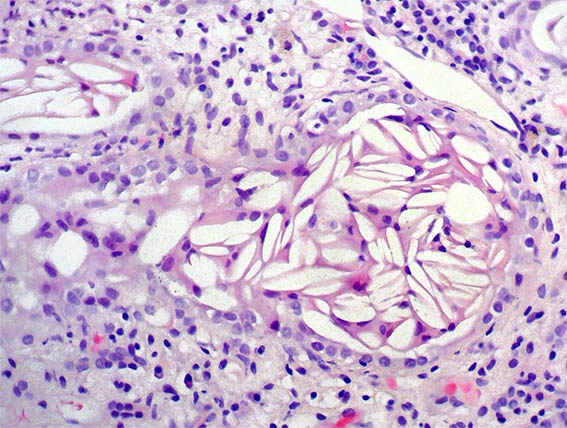

Figure 4. H&E, X100.

Figure 5. Masson's trichrome stain, X100. Observe what is in some tubules, which are very dilated.